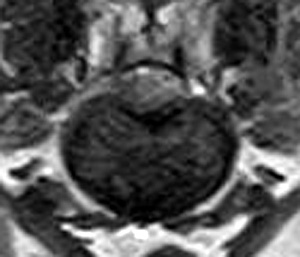

市内の先生からダックスちゃん両後肢麻痺グレード5でMRI検査及び手術依頼でご紹介がありました。MRI検査で第13胸椎-第1腰椎間椎間板ヘルニア、右側優位な圧迫と診断し手術となりました。→<その2>へ続く